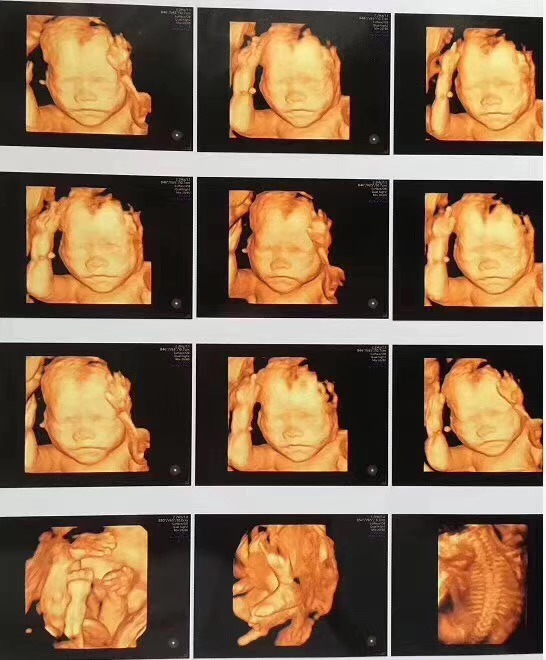

四维彩超

佛山都市妇产医院妇产科主任提醒:超声影像(四维彩超)检查的合适时间单胎为孕22—26周,双胎为孕20—24周,此时胎儿已经基本发育成形,局部结构和运动状态都可以清晰地观察到,可发现胎儿发育异常,比如无脑儿、脊柱裂、内脏外翻、单腔心、致死性软骨发育不良等。

GE四维彩超

佛山都市妇产医院引进美国GE四维彩超,画面更清晰,排畸更准确,能够全方位、多角度检查胎儿的生长发育情况,孕妈妈可以通过四维彩超与宝宝提前见面,感受生命最初的感动。